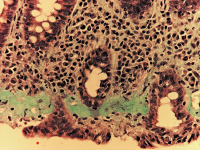

Kollagene Kolitis

Abbildung 2: Histologisches Beispiel einer kollagenen Kolitis mit verdicktem subepithelialem Kollagenband (Goldner-Färbung).